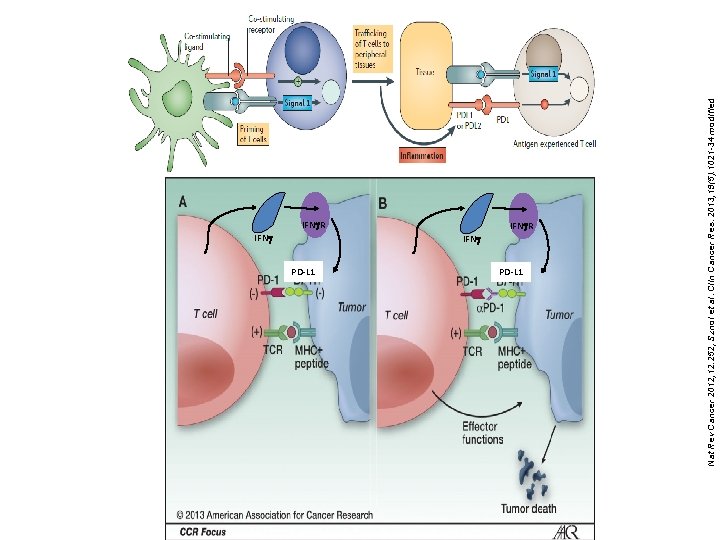

IFNg. R IFNg PD-L 1 IFNg. R PD-L 1 Nat Rev Cancer 2012; 12: 252, Sznol et al. Clin Cancer Res. 2013; 19(5): 1021 -34 modified IFNg

Neo-antigen Hypothesis • Neo-antigens are mutant proteins in cancer (10 s to 1000 s per cell), and can be catalogued by DNA sequencing • Are seen as foreign proteins and cells expressing them are attacked, except…. • Tumor cells have co-opted the normal tolerance mechanisms used to avoid autoimmunity (checkpoints) • Immunotherapy works because of tolerance blockers or neoantigen-specific T cells or vaccines Schumacher and Schreiber, Science 2015